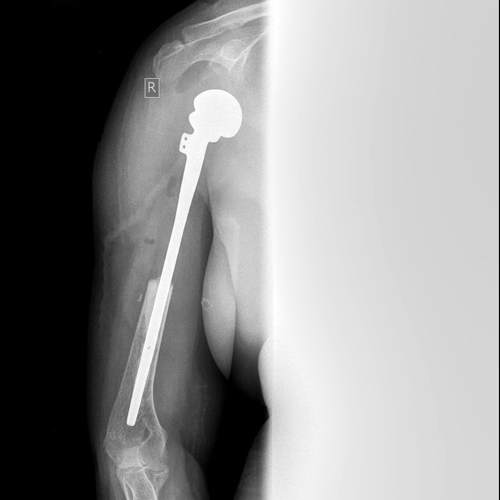

Հիվանդ Ս., 52 տ., 08.12.15թ. ընդունվել էբժշկական կենտրոն գանգատվելով աջ ուսային գոտու շրջանի ցավերից և նշված հոդում շարժումների խիստ սահմանափակումից: Անամնեզ` 5 տարի: Բազմաթիվ անգամ դիմել է բժիշկներին, սակայն համապատասխան հետազոտություն չի անցկացվել: Համալիր հետազոտման արդյունքում հիվանդի մոտ ախտորոշվել է` աջ բազկոսկրի պրոքսիմալ հատվածի խոնդրոսարկոմա:

Ըստ ԿՏ-հետազոտության, հայտնաբերվել է ներոսկրային ուռուցքային ախտահարում 15 սմ երկարությամբ: Ուսագոտու մկանների ներգրավվածություն պրոցեսի մեջ չէր հայտնաբերվել:

08.12.15թ.բժշկական կենտրոնի առաջատար մասնագետ` ուռուցքաբան-վնասվածքաբան, բ.գ.թ. Սարգիս Նազարի Մարգարյանի ղեկավարությամբ, ընդհանուր անզգայացման տակ, կատարվել է բազկոսկրի պրոքսիմալ 2/3 սեգմենտար ռեզեկցիա էնդոպրոթեզավորումով: Մկանային կարկասի ինտակտ լինելը թույլ տվեց լիովին վերականգնել նրանց անատոմիան, հատկապես ենթաթիակային մկանը, որն ունի մեծ դեր ուսային հոդի ֆունկցիայի և կայունության մեջ:

Մակրոպրեպարատի հիստոլոգիական եզրակացությունը`Հասարակ խոնդրոսարկոմա (grade I). Վիրահատական ռադիկալիտետը լիարժեք է (R0):